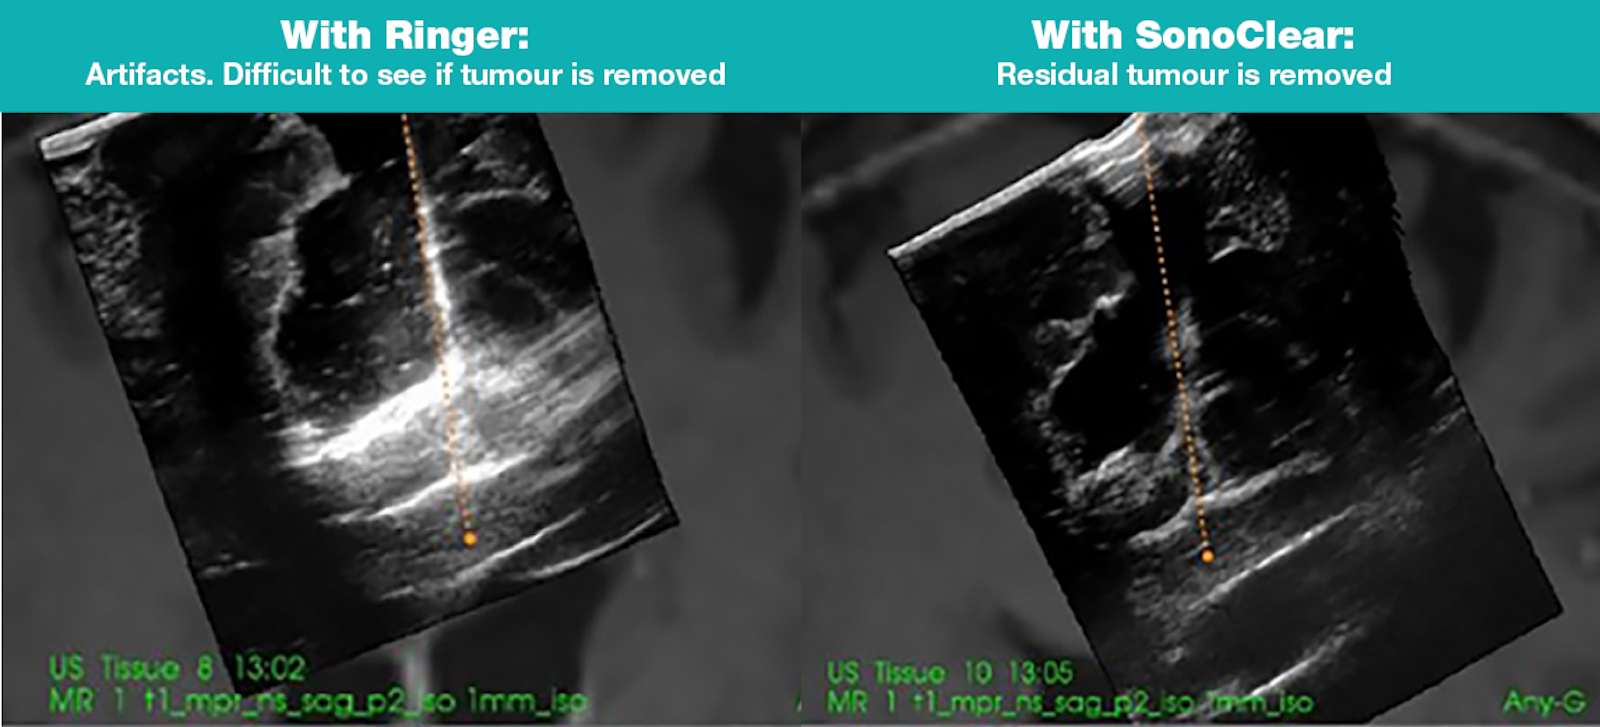

SonoClear AS develops an acoustic contrast fluid to remove noise in ultrasound images, used during brain tumor surgery to guide tumor removal. The goal is to be sure that all tumor is removed, as total resection improves patient outcomes. The technology is developed by neurosurgeons at St.Olavs hospital and engineers at Sintef. The technology is patented worldwide and is developed as a medical device according to ISO13485. The core team consists of CTO, Medical advisor, Quality manager, and Regulatory officer. SonoClear plan for market access in USA and EU in 4q20 and 4q21, respectively.